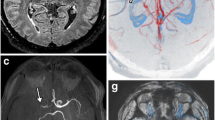

Illustrative case of arterial hyperintensity with multimodality images

A 62-year-old man presented with left-sided weakness with an initial NIHSS score of 10. CT angiography and digital subtraction angiography showed occlusion in the right MCA, insular segment. Hyperintense artery was visualised distal to the occlusion site on post-contrast 3D T1W BB FSE, and not on the pre-contrast study. The velocity of hyperintense artery appeared to be slower than that of the vein, since the signal intensity of the posterior superior sagittal sinus was suppressed. Hyperintense artery was well matched with the retrograde collateral flow on digital subtraction angiography (Fig. 1).

a Maximum intensity projection image of CT angiography shows occlusion in the right MCA, insular segment (arrow). b Maximum intensity projection image of Gd-enhanced 3D T1W BB FSE shows hyperintense arteries (arrowheads) distal to the occlusion site. c Angiography in early phase shows occlusion in the right MCA, insular segment. d Retrograde collateral flow is filled in the delayed phase at the region where the hyperintense artery is seen. Hyperintense artery is not seen on the pre-contrast (e) but on the post-contrast 3D T1W BB FSE (f)

This study showed that in patients with acute MCA stroke, the hyperintense artery sign on Gd-enhanced 3D T1W BB FSE may have resulted from a retrograde slow collateral flow and was well matched with the FLAIR hyperintense vessel sign, but showed a better contrast. The patients with hyperintense artery in a wider territory showed higher perfusion deficit than those with hyperintense artery in a narrower territory.

Gd-enhanced high-resolution black-blood T1-weighted imaging has been commonly used in stroke, and Jang et al showed that it improves detection of intraluminal thrombi [37]. However, hyperintense artery signs are rarely mentioned [13, 38,39,40]. Hui et al first mentioned the hyperintense artery sign as a “white snake sign” and they presumed that this sign may be due to a sluggish slow flow and just distal to a thrombus [41]. Our results agree with those of the previous study. Hyperintense artery corresponds to a sluggish collateral flow. This retrograde slow flow may result in loss of the flow void phenomenon, and vessels may appear hyperintense against the dark CSF background [42, 43]. However, according to our results, a collateral flow did not appear hyperintense on non-enhanced 3D T1W BB FSE. This implies that the appearance of hyperintense artery cannot be explained only by loss of the flow void phenomenon. We presume that the T1-shortening effect of Gd contributes to the underlying loss of the flow void phenomenon, making sluggish flows hyperintense.